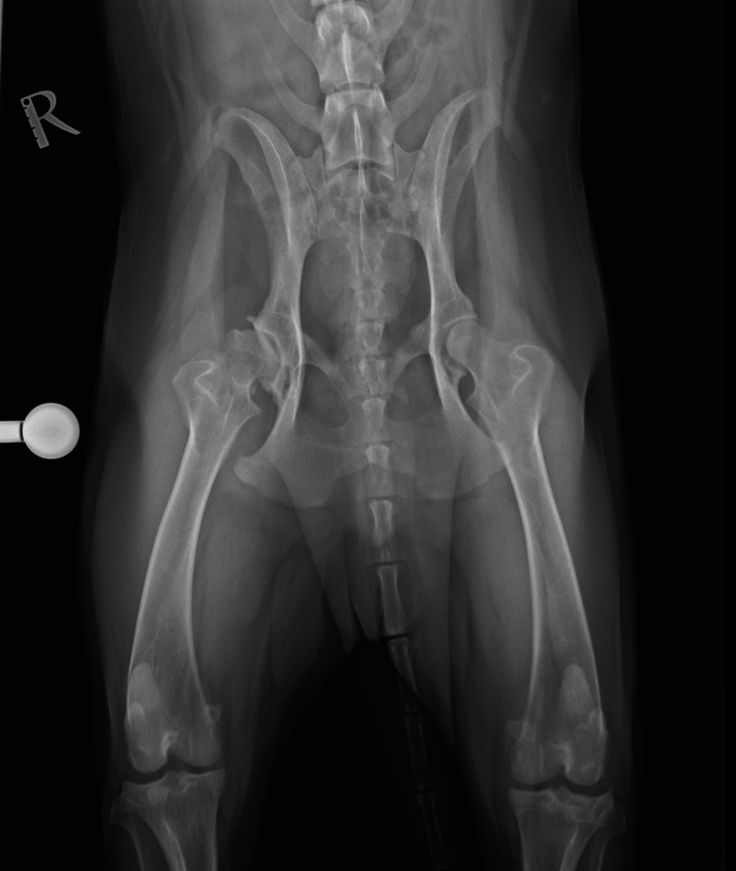

レントゲンの結果、両足の股関節形成不全が確認され、今後を考えると歩けなくなる可能性が高く、元のように歩けるには(人工関節全置換手術)を受ける必要があるとの事でした。

今後の流れとしては、次に股関節形成不全の治療で(人工関節全置換術)を受けるのがベストとの事でした。

※10/13に股関節形成不全のため(人工関節全置換術)をうけます。(片方のみ)

右股関節形成不全(人工関節全置換術)

検査費込み(片方の脚のみ) 110万円

股関節形成不全(人工関節全置換術) 110万円

私、護得久 美奈が飼っているシェパード雄、4歳が 2024年10/13に県外の動物病院で股関節形成不全により人工関節手術(股関節全置換術)をうけます。 退院予定10/25 ※レオンの体調により前後します。 ※資金はすべて医療費、人工関節全治置換手術、入院費、術前検査費、処置費に使わさせて頂きます。 ※飛行機など交通費は自己負担